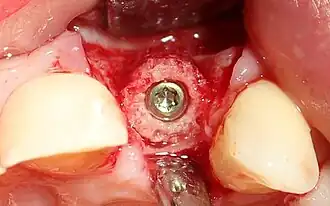

Die Knochenringtechnik erfolgt im Allgemeinen in Lokalanästhesie und unter ambulanten Bedingungen. An der zu implantierenden Stelle wird zunächst die Schleimhaut aufgeklappt und der defekte Knochen des Kieferkamms vermessen. Dann wird mit einer passenden Trepanfräse ein Knochenring an anderer Stelle entnommen (siehe auch Entnahmestellen der Knochenringe) oder ein allogener Knochenring verwendet. Als nächster Schritt wird in dem zu implantierenden Gebiet die Pilotbohrung für die Implantatausrichtung vorgenommen. Es wird dann mithilfe einer passenden Trepanfräse mit zentralem Pin das Lager für den einzusetzenden Knochenring zentriert geschaffen. Der Knochenring kann dann in den meisten Fällen im Press-Fit Verfahren eingesetzt werden. Die weitere Implantatbohrung wird dann entsprechend individuell festgelegter Länge und Durchmesser durch den Knochenring hindurch vorgenommen. Das Implantat wird nun durch den Knochenring in den Kieferknochen langsam und mit geringem Druck bis zur gewünschten Position eingeschraubt. Sofern jetzt noch keine Primärstabilität des Knochenringes vorliegt, kann diese durch die Verwendung einer Deck- oder Membranschraube durch axiale Kompression erreicht werden. In der Regel wird anschließend das OP Gebiet mit einem langsam resorbierbaren Knochenersatzmaterial und einer Membran abgedeckt. Ein speicheldichter Wundverschluss beendet die OP. Nach einer Einheilzeit von ca. einem halben Jahr kann die prothetische Versorgung des Implantates erfolgen.